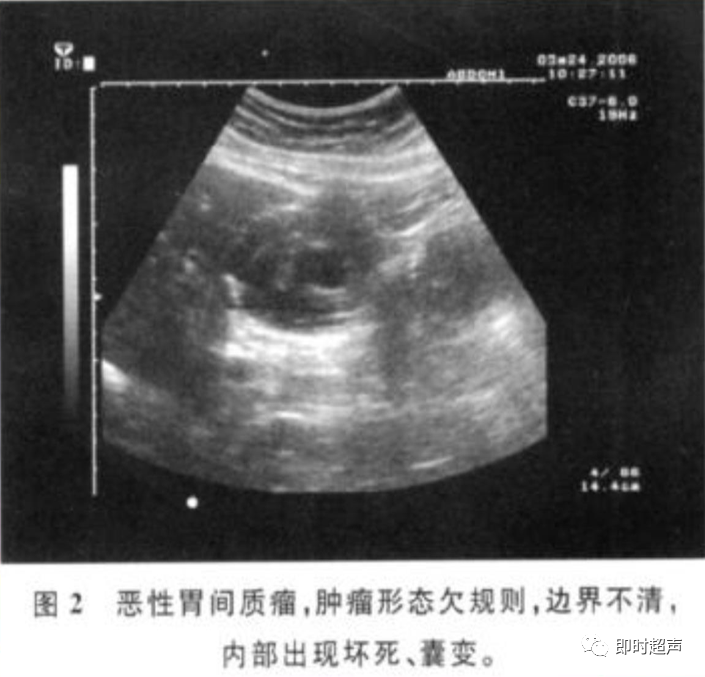

• GIST的发病机制与KIT信号通路的激活有关。• KIT是一种酪胺酸激酶跨膜受体蛋白,未经“装配”过的KIT蛋白是一种非活化的单体,参与细胞膜形成。几乎所有GIST都表达了KIT蛋白,而且大多突变的KIT基因保留了表达KIT蛋白的特性。c-kit内的突变主要见于恶性病例,特别是外显子11的点突变,还有外显子9、13和17,可以导致本质的或配体独立的c-kit激活,引发细胞的无序增殖和凋亡。这些具有功能的突变是GIST发病机理的关键,并且与肿瘤的恶性程度和预后较差相关。• GIST约75%发生于50岁以上老年人,中位年龄为58岁,无明显差异。• 可以发生在消化道从食道到肛门的任何部位,偶尔可原发于网膜、肠系膜和腹膜后,约50%发生在胃,25%发生在小肠,不足10%发生于食管、结肠及直肠。大体观察:肿块多境界清楚,类圆形,结节状,部分有假包膜。切面灰白、灰红,质韧,部分质嫩呈鱼肉状,伴有出血、坏死、囊性变。• 肿瘤组织主要由两种细胞组成,一种为长梭形细胞,细胞质丰富,嗜酸性,细胞核呈梭形或杆状;另一种为上皮样圆形或多角形细胞,细胞肥胖,胞质少。两种瘤细胞常呈束状、编织状或旋涡状排列。• 部分病例细胞异型明显,核分裂象增多,可见病理性核分裂象和瘤巨细胞。梭形细胞界不清楚,胞质丰富,淡染,轻度嗜伊红或略嗜碱,可有纤细、长梭形、短梭形或胖梭形、卵圆形,可见核仁。细胞核两端钝圆,部分病例胞质呈空泡状,位于核一端形成核端空泡胞,多呈交叉束状、旋涡状、席纹状及栅栏状排列。上皮样细胞胞浆丰富或透亮,多呈弥漫片状、束状或巢状排列。肿瘤间质可有出血、囊性变、坏死及黏液变,可见炎性细胞浸润。CD34抗原是一种115kd的糖基化蛋白,50%~80% GIST的CD34表达为阳性,CD34对鉴别GIST和典型的平滑肌瘤,神经鞘瘤还是非常有用的标记物,因后两者的CD34一般是阴性的。但CD34在诊断GIST上其特异性受到限制,一般情况下CD34多与CD117联合应用,方能提高GIST的诊断率。• 与肿瘤大小、发生部位、肿物与肠壁的关系以及肿瘤的良恶性有关。• 肿瘤较小者(直径小于2cm)常无症状,往往在体检和其它手术时无意中发现。• 肿瘤发生于胃肠道腔内时大多表现为呕吐、腹痛及消化道出血,而发生于胃肠道腔外的则主要表现为腹部包块。• 最常见的临床症状是中上腹部不适、腹部肿块及便血。• 对于临床发现的消化道(包括肠系膜、网膜、后腹膜)实体肿瘤,在排除其他常见肿瘤后,才考虑GIST。目前,诊断GIST有三条标准:③肿瘤组织具有梭形细胞和上皮样细胞两种基本细胞成分的病理学特征。这是诊断GIST金标准。CD117阳性者或CD117阴性而CD34阳性者,且伴平滑肌和神经双向分化或无分化者,可诊断为GISTs;以Desmin和SMA强阳性,而CD117阴性诊断为平滑肌肿瘤;以S-100阳性,CD117、Desmin、SMA均阴性诊断为神经鞘瘤。• GISTs的分型与组织学良恶性的关系:研究证实GISTs非单一分化的肿瘤,具有多向分化。• 当前GISTs的良性、交界性和恶性判断标准多参照Amin等提出的标准:②交界性:核分裂<5/50HPF,但肿瘤>5cm;• 另外研究显示,平滑肌型大多数为良性,少数为交界性和恶性,神经源型为恶性,双向分化亚型和未分化型为交界性和恶性,提示GISTs的分化型与其良恶性之间有一定关系。• 胃间质瘤早期多局部侵犯,后期出现肝转移和腹腔内种植,小肠间质瘤早期即可出现转移• 主要有超声扫描(检出率30%左右)、纤维内镜、超声内镜、CT、MRI、普通X• 线检查(胃肠钡餐造影、小肠插管气钡双重造影)、选择性血管造影检查等。• 不同部位的GIST,各种检查方法的敏感性不同。以CT检查为佳,尤其是螺旋CT,分辨率最高,可以三维重建,直接显示肿瘤大小、形态、密度、内部结构、边界,对邻近组织的侵犯也看得很清楚,同时还可观察其他部位的转移灶,有利于分期、鉴别与诊断。• MRI具有多轴成像及反映肿瘤内部成分的优点,尤其是动态扫描及各种新的扫描系列的出现更使其可以普及应用。• DSA检查对于GIST,特别是有消化道出血的患者更有价值。• 上述影像学检查表现并非特异性,与胃肠道平滑肌肿瘤、神经源性肿瘤鉴别困难。明确诊断要依赖病理免疫组化等手段。• 超声图像特征 肿物体积较小者(直径< 5. 0 cm )多为实性病变, 呈类圆形, 边界清晰, 内部回声多为较均匀的低回声。• 肿物体积较大者(直径> 5. 0 cm ) 多为混合性病变,呈不规则圆形或分叶状, 多数边界尚清晰, 以实性为主的病变内部为不均质中低回声伴不规则液性区及斑点状强回声; 以囊性为主的病变囊壁较厚,有分隔, 部分囊腔内可见点状、团状低回声。CDFI显示肿物实质回声内血流均较丰富。病例1:患者男, 62岁。自扪腹部包块2月余,包块增大20天就诊。查体:腹部平坦,无腹壁静脉曲张,无胃肠型及蠕动波,腹肌软,剑突下5cm处及左肋缘下可触及一质韧包块,大小约15*12cm,活动度差,边界尚清,包块深压痛,全腹无反跳痛。化验检查AFP:3.66(1.09-8.04)ng/ml,CEA:2.85(0-5)ng/ml。体格检查:一般情况良好,全腹软、平坦,腹部无压痛。超声检查:患者仰卧位时左上腹于胰尾前方可见一大小约6. 1 cm ×5. 8 cm ×5. 3 cm实性均质低回声,形态规则,包膜完整,边界清晰,活动度大;右侧卧时,肿块移至胰头右前方(图1) ;于其内探及丰富血流信号。体格检查:一般情况良好,腹丰满,上腹部有轻压痛,未扪及明显肿块。超声检查:患者仰卧位时左上腹于胰尾前方、脾门处可见一大小约10. 0 cm×8. 8 cm×7. 6 cm 实性低回声(图2) ,形态规则,包膜完整,边界清晰,肿块活动度大;右侧卧时,肿块移至左肝下间隙,回声尚均质;于其内探及较丰富血流信号(图3) 。图3 腹腔低回声肿块位于左肝下间隙,于低回声肿块内探及较丰富血流信号向壁外生长的胃肠道间质瘤, st为胃腔,箭头所指为胃壁, T为向外生的肿瘤• 胃间质瘤的定位准确率要高于十二指肠及小肠间质瘤,这主要是因为胃的解剖位置相对固定,且通过饮水使胃腔充盈,可清晰的显示胃壁的各层结构及肿块与胃壁的关系。肿块多表现为粘膜下、肌层或浆膜下低至中等回声团块,可向腔内、腔外或腔内外生长。但当肿瘤较大或浸润周围脏器时,超声定位仍有困难, 因此,超声如发现上腹部肿块且怀疑来源于胃者,应尽可能嘱其饮水充盈胃腔,并多角度、多切面观察肿块与周围脏器的关系,以提高定位的准确性。• 十二指肠间质瘤的定位亦较准确,但降部的外生性肿块常与胰头粘连而误诊为胰腺肿瘤回声均匀且位置较深的间质瘤亦可能误为胰头周围淋巴结。• 空、回肠间质瘤常因肿块较大,多发,位置不固定而难以定位,往往误诊为腹、盆腔或腹膜后肿瘤,超声检查如发现肿块局部肠壁增厚,肿块与肠道随呼吸同步运动时可作出定位诊断。• GIST的声像图表现有助于其良、恶性的鉴别:良性肿瘤多体积较小,圆形或椭圆形,回声均匀,边界清晰。恶性肿瘤多较大,呈不规则分叶状,回声不均匀,内部易出血、坏死、囊变。• 肿瘤长径与肿瘤内部是否出现无回声区在良、恶性病变之间的差异有统计学意义,是判断良恶性的有效征象。• 如以肿瘤长径>5cm为诊断恶性标准,其敏感性、特异性及准确性均较理想。超声可为临床提供胃肠道间质瘤的部位、大小、边界、回声等较多有用信息,一部分病例可作出定位、定性诊断,并可在术后或复发患者药物治疗期间对其进行动态观察;CDFI方便快捷、无需造影剂即可对间质瘤周边及内部血流进行观察,可为临床医师提供肿瘤血供情况。但未发现腹腔或肝脏转移时,超声判断胃肠道间质瘤性质有一定难度。• 目前临床上对GISTs的治疗效果并不十分满意。治疗仍以手术为主,对无法手术切除或已有转移的GISTs患者进行甲磺酸伊马替尼化疗。• 手术方式取决于肿瘤大小、部位和术中冰冻切片结果等。• 发生在胃的间质瘤,可首选胃大部切除术;发生在十二指肠的间质瘤可行保留胰头的十二指肠切除术或胰十二指肠切除术;发生在小肠的间质瘤可行肿瘤肠段切除术;发生于结肠的间质瘤可行左半或右半结肠切除术;发生于直肠的间质瘤可行肿瘤局部切除术。一般情况下无需淋巴结清扫。• 术后随访监测,复发者单个病灶可考虑手术切除;多发或转移特征者应试行甲磺酸伊马替尼化疗,并监测肿瘤大小及数目的改变。• 随着分子靶点药物进入肿瘤临床,一种小分子化合物———酪胺酸激酶受体抑制剂,美国称为Gleevec,欧洲叫做Glivec(格列卫),在治疗GIST和慢性粒细胞白血病方面有其独特的作用。已知细胞膜表面上皮生长因子受体酪胺酸激酶抑制剂大致分为两大类:一类是小分子化合物;另一类是特异性抗体。利用抑制酪胺酸激酶的活性,对处于增殖期状态的病变具有治疗的作用。Glivec在体外、体内和细胞水平都可强烈抑制酪胺酸激酶的活性,是干细胞因子(SDCF)受体KIT的强抑制剂。• Glivec推荐用量为400mg(4片),每日一次, 3个月为一疗程。如服3个月后无效可加至600mg/d~800mg/d(6~8片)[18];若仍无效果不再增量应停止治疗。• Glivec治疗进展转移的GIST总有效率为50%左右,比传统化疗有效率高十倍以上;肿瘤生长控制率达80%以上,起效最快在服药后24h之内,使症状改善如疼痛缓解;平均起效时间为13周(约3个月)。患者体力状况改善是又一突出效果。2/3患者治疗后无症状可如健康人生活工作。• Brainard等研究发现间质瘤预后差的前两位因素为肿瘤大小和核分裂象,故对于间质瘤直径>5cm和核分裂象>5/50HPF的患者应给予口服Glivec。最近,Liu报道口服Glivec治疗可使85%患者的病情得到控制。